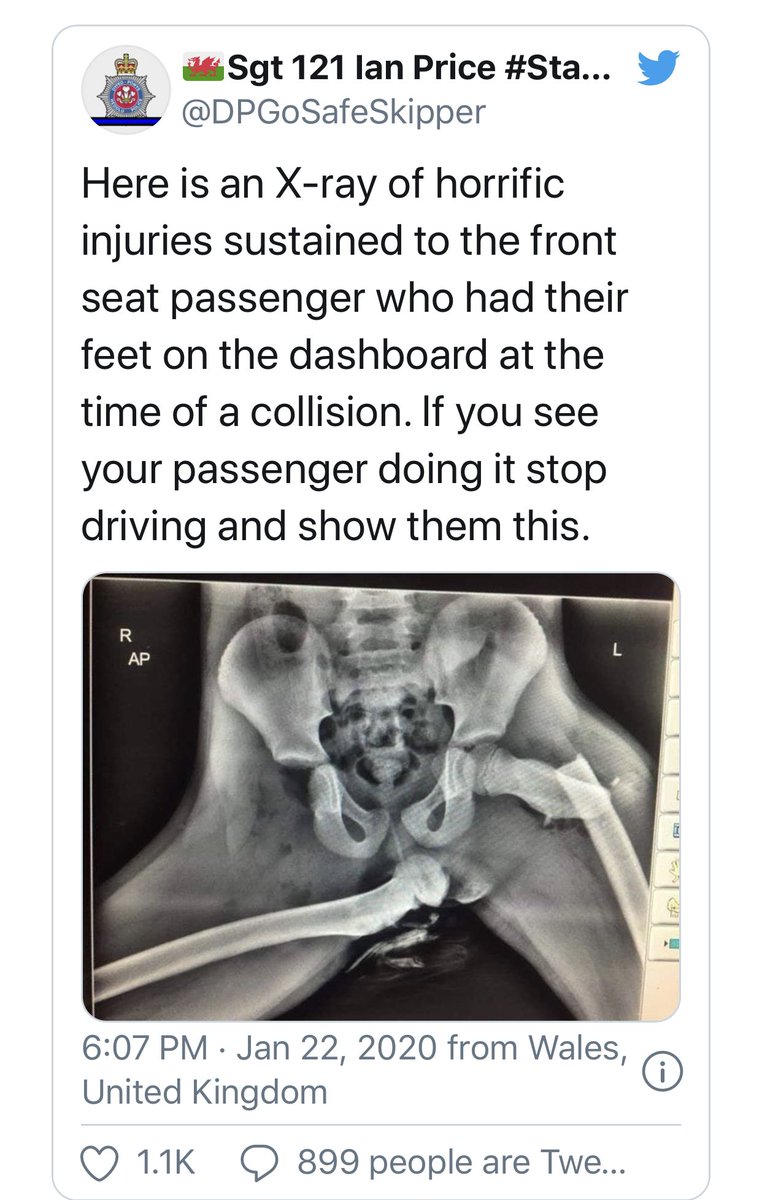

Avec la caution Police, le message est encore plus fort ... "Police share shocking X-ray to show why you should not put your feet on car dashboards"

Vous remarquerez si vous cherchez que c& #39;est toujours la meme image, celle-ci  https://abs.twimg.com/emoji/v2/... draggable="false" alt="👇" title="Rückhand Zeigefinger nach unten" aria-label="Emoji: Rückhand Zeigefinger nach unten">